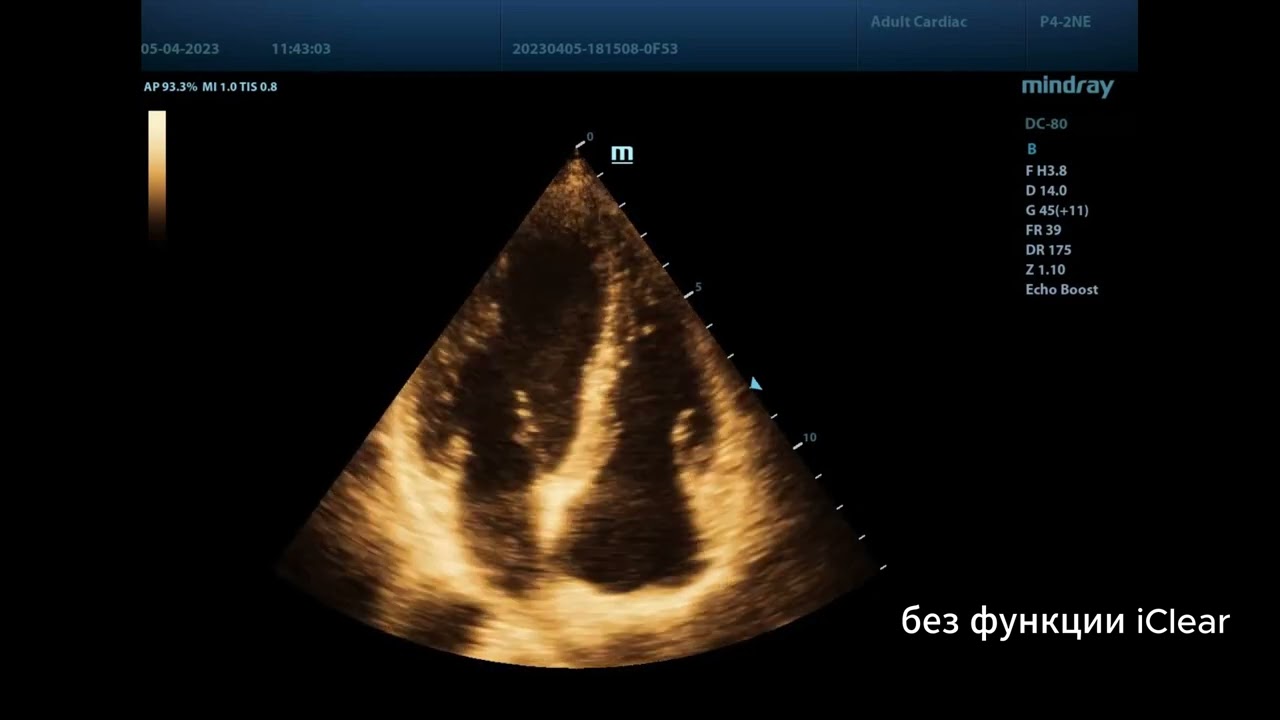

Пример изображения на экспертном приборе Mindray DC-80 X-Insight, это апикальное сечение в эхокардиографических исследованиях. Несмотря на то, что это один и тот же пациент, видео выглядит по-разному. Причина этого явления – функция iClear.

Функция служит для усиления изображения, сглаживания однородных тканей, подавления артефактов спекл-шума и «очистки» анэхогенных зон, а также улучшения распознавания границ структур и тканей. Аппарат предоставляет семь уровней регулировки iClear, чем больше значение, тем сильнее эффект.